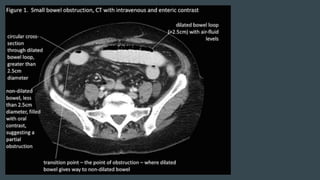

CT SCAN

PRESENCE OF OBSTRUCTION

LOCATION, SEVERITY, AND

CAUSE

RADIOLOGICAL PICTURE

Small Bowel Obstruction

Central distention (GAS)

Valvulae conniventes

Ladder-like dilatation

Small diameter

Large Bowel Obstruction

Peripheral distention “Picture frame”

More gross distention

Haustral indentation & large diameter

In most cases, the abdominal

radiograph will have the following

features:

1. Dilated loops of small bowel

proximal to the obstruction

2. predominantly central dilated

loops

3. dilatation of loops over 3cm

4. valvulae conniventes are visible